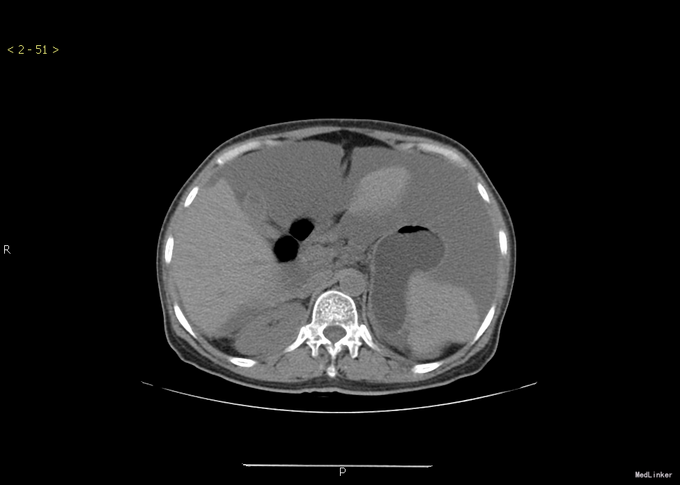

查体:腹部膨隆,腹部张力大,无压痛,无反跳痛,移动性浊音阳性。其余无特殊。 胸部+全腹部CT示:1.胸部增强扫描未见明确异常。2.盆腔底部腹膜明显不规则增厚,右侧附件可见肿块,考虑卵巢肿瘤可能。3.腹盆腔大量积液。

诊断:卵巢钎维瘤合并麦格综合征 治疗:行腹腔积液引流后,腹水未发现肿瘤细胞。后行全子宫双附件切除术。术后病理提示:卵巢纤维瘤。手术顺利。